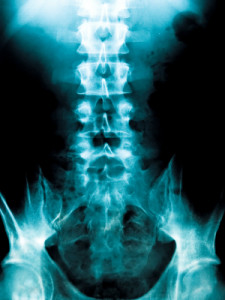

По форме искривления сколиоз делится на три группы:

С-образный сколиоз (с одной дугой искривления)

S-образный сколиоз (с двумя дугами искривления)

Z- образный сколиоз (с тремя дугами искривления)

Сколиоз от латинского слова «кривой», scoliэsis Pозначает боковое отклонение позвоночника от нормального прямого положения.

Сколиоз обычно развивается в периода роста. Он начинается и прогрессирует в юности, во время усиленного роста тела. Примерно в 80 % всех случаев причина возникновения искривлений неизвестна.